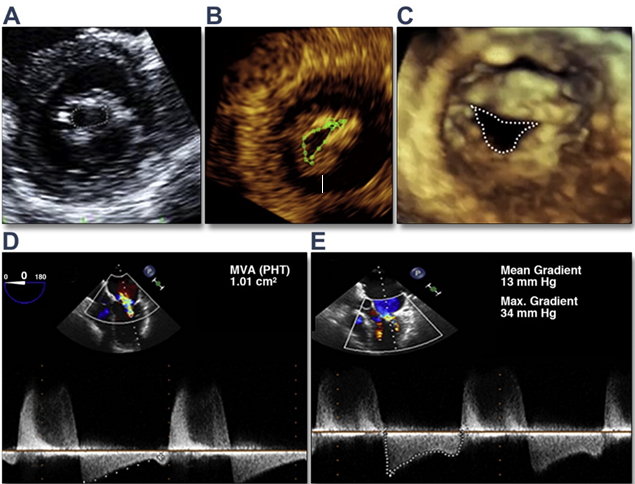

L’âge moyen était de 26,68 ± 7,36 ans. Le sex-ratio était de 0,2 avec une prédominance féminine dont 83,3% de femmes. Deux patientes présentaient une grossesse évolutive de 16 et 21 SA. Une dyspnée stade II à IV était présente chez tous les patients (NYHA). L’électrocardiogramme inscrivait un rythme sinusal chez trente-six patients et quatre en arythmie complète par fibrillation auriculaire. Deux patients ont eu un flutter auriculaire en per-procédure qui a régressé sous choc électrique externe. Le temps de procédure moyen était de 39,62 mm +/- 45,38 et de 8,37 mn pour les deux patientes en état de grossesse. Quatre patients ont eu une baisse du gradient trans-mitral et des pressions pulmonaires mais avec une augmentation peu importante de leur surface mitrale. Aucun échec de procédure n’a été noté. La radiographie thoracique de face montrait un index cardiothoracique moyen à 0,57 ± 0,06.Le diamètre moyen du ballon était de 27,47 ± 1,23 mm. En pré-dilatation, la surface mitrale (SM) moyenne était de 0,68 ± 0,15 cm2 vs 1,47 ± 0,39 cm2.en post dilatation (p=9.44e-08).Une augmentation de la surface mitrale en post procédure a été notée dans tous les cas. (Figure5).

L’estimation par échocardiographie Doppler du gradient moyen montrait que le GM passait de 16,03 ± 6,83 mmHg à 5,35 mmHg ± 2,03 (p=1.714e-07) (fig6).

A l’écho-Doppler post-procédure, on notait une diminution des pressions pulmonaires (PAPS) évaluées par le flux d’insuffisance tricuspide de 73,14 mmHg ± 26,86 à 50,1 mmHg ± 18,5 (p=2.672e-06).La figure 3 illustre les courbes des PAPS avant et après dilatation.

Figure 1 : Mesures échographiques de la surface mitrale et du gradient Trans mitral